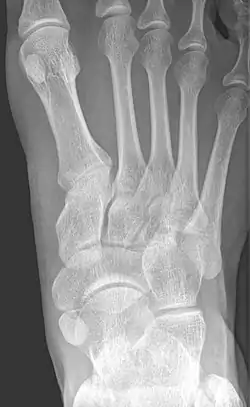

Radiological images

From left to right: Type 1, 2 and 3